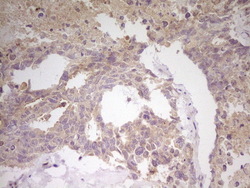

Supportive validation

- Submitted by

- LSBio (provider)

- Enhanced method

- Genetic validation

- Main image

- Experimental details

- IHC of paraffin-embedded Human testicular cancer tissue using anti-CITED1 mouse monoclonal antibody. (Heat-induced epitope retrieval by 1 mM EDTA in 10mM Tris, pH8.5, 120°C for 3min).